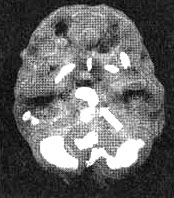

Результаты сканирования SPECT у Сэлли

Снимок в горизонтальной плоскости — мозг в состоянии покоя. Обратите внимание на хороший уровень активности в префронтальной области (отмечено стрелками).

Снимок в горизонтальной плоскости во время концентрации. Обратите внимание на выраженное снижение активности, особенно в префронтальной коре.